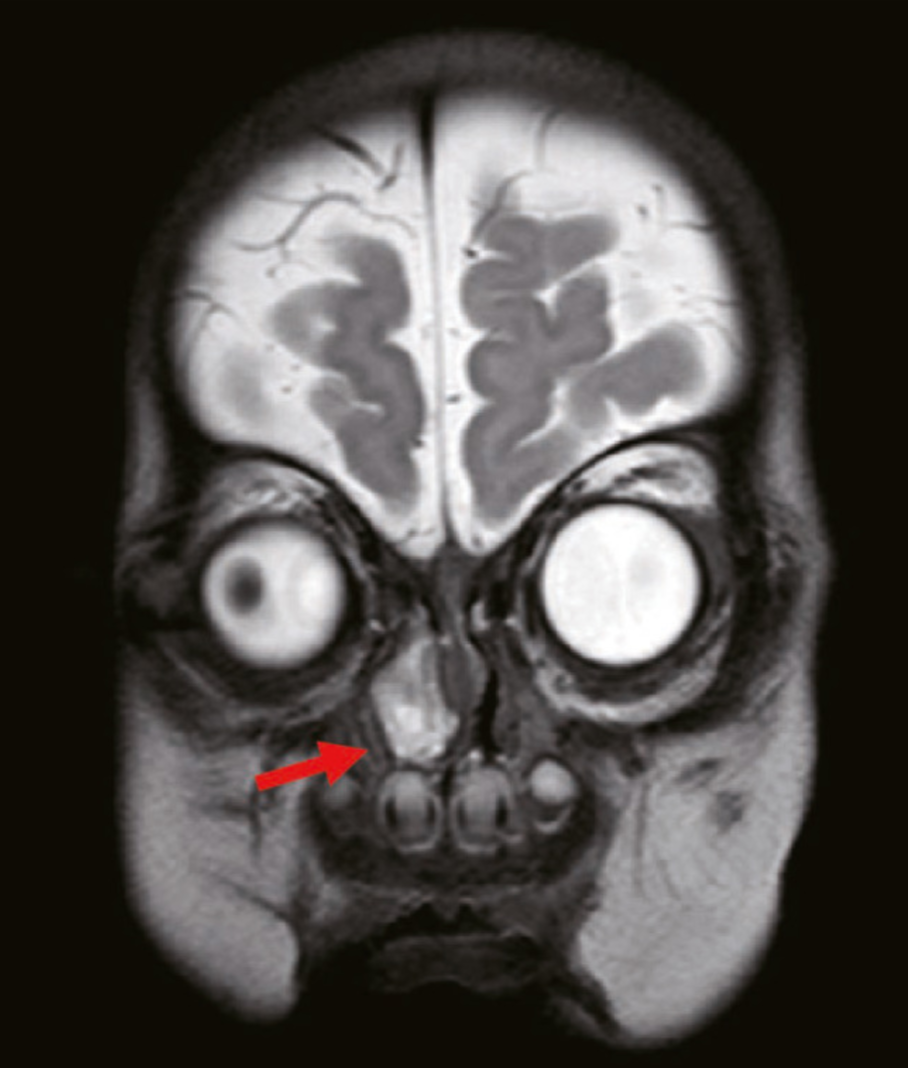

一名2个月大的男孩因出生后出现的鼻塞而接受治疗。右侧鼻腔阻塞明显,持续存在,并逐渐加重,导致奶瓶喂养时窒息。纤维支气管镜检查显示右鼻腔靠近咽部有2.0cm×1.5cm的息肉样物质(图1)。鼻咽计算机断层扫描(CT)显示右鼻腔软组织中有小面积高密度影。

肿块的放射密度约为26-35个Hounsfield单位,未见明显增强;此外,颅底无明显骨缺损,肿瘤与大脑不相通。磁共振成像(MRI)显示右侧鼻腔和前庭软组织有高密度影(图2)。软组织肿块大小约为22.1mm×17.3mm×10.9mm,呈不均匀强化。此外,肿块延伸至右鼻骨后部,并与鼻中隔和鼻骨(右下鼻甲附着于肿块的外侧边缘)粘连。鼻中隔左侧稍凸出弯曲,右侧鼻道增宽;右侧鼻骨稍塌陷变形,右侧上颌窦腔稍狭窄。肿块底部从鼻腔侧壁延伸,肿块前界位于下鼻甲前端水平,肿块后界位于中鼻甲后端水平。肿块的上边界距离鼻咽顶部约2-3毫米。肿块整体呈息肉样。术前诊断为先天性鼻内肿瘤。

图2